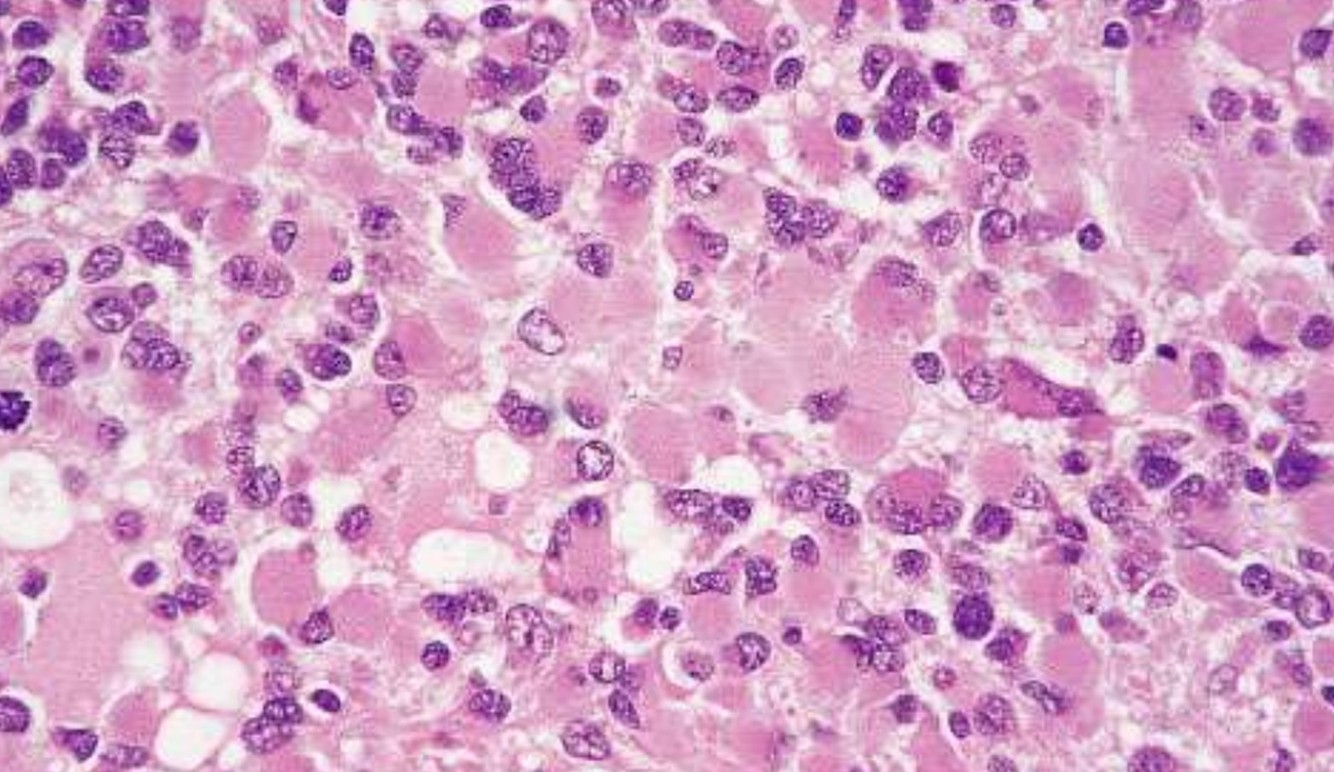

Poorly Differentiated/ Embryonal Tumors

Poorly Differentiated/ Embryonal Tumors

- Malignant small blue cell tumors

- Grade IV

- Young Children

Medulloblastoma

- 20% of pediatric brain tumors

- Posterior fossa

- Spreads by CSF seeding along the subarachnoid space

Primitive Neuroectodermal Tumor

- Supratentorial tumors

- Histologically identical to medulloblastomas, genetically differ from medulloblastomas and peripheral PNET (lack Ewing’s translocations)

- Homer-Wright rosette

Atypical Teratoid/Rhabdoid tumor

- 2% of pediatric brain tumors

- Highly malignant of young children/infants (up to 5 years of age)

- “Rhabdoid” cells

- Multiple lineage markers (epithelial , muscle)

- Molecular Genetics: >90% of cases show loss/mutations of hSN5/INI1 gene on chromosome 22

- IHC: loss of normal nuclear staining for INI1